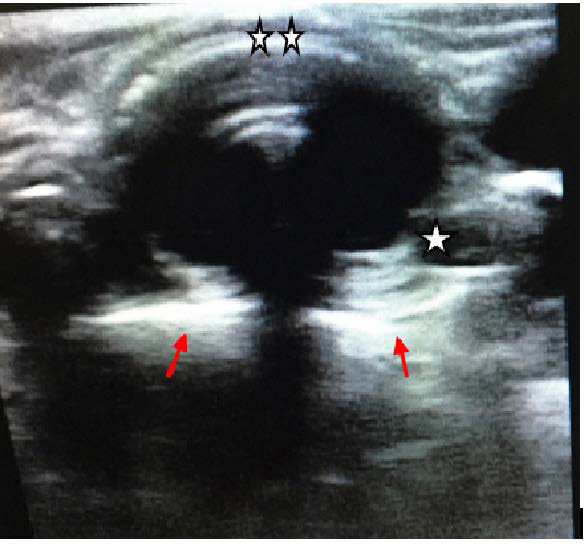

Figure 2: Ultrasound image demonstrating shadows representing saline-filled cuff of endotracheal tube.

Trachea (☆ ☆) , Esophagus (☆) , Shadows of saline-filled cuff (red arrows).